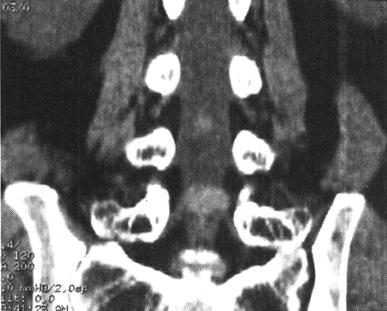

CT在脊柱脊髓损伤中应用很广泛,横断面成像是诊断脊椎骨结构创伤的主要手段,它可显示X线平片不易显示的细微骨折和小关节脱位,并能够很好地显示骨性椎管的情况,可为评价脊髓受压情况提供重要的影像学信息。螺旋CT扫描技术可对患者进行快速连续多部位成像,并支持多平面及三维成像。因而CT扫描对理解脊柱复杂解剖部位,发现细微病变有十分重要的临床意义(图7-4至图7-6)。甚至明显侧弯变形脊柱的冠状面重建亦可通过严格按照脊柱弯曲度改进的软件而获得。单纯轴位扫描很容易漏诊与CT断层面平行的骨折,例如,发生在齿突基部和胸腰水平的创伤,在横断位扫描中不能显示横断水平的骨折线,但在高质量的冠状、矢状和三维的重建图像中显示良好(图7-7至图7-10)。

图7-7、图7-8 多排螺旋CT2D重建,显示C2齿状突基底部骨折

图7-9、图7-10 多排螺旋CT3D重建,显示骨折线走行及累及骨表面